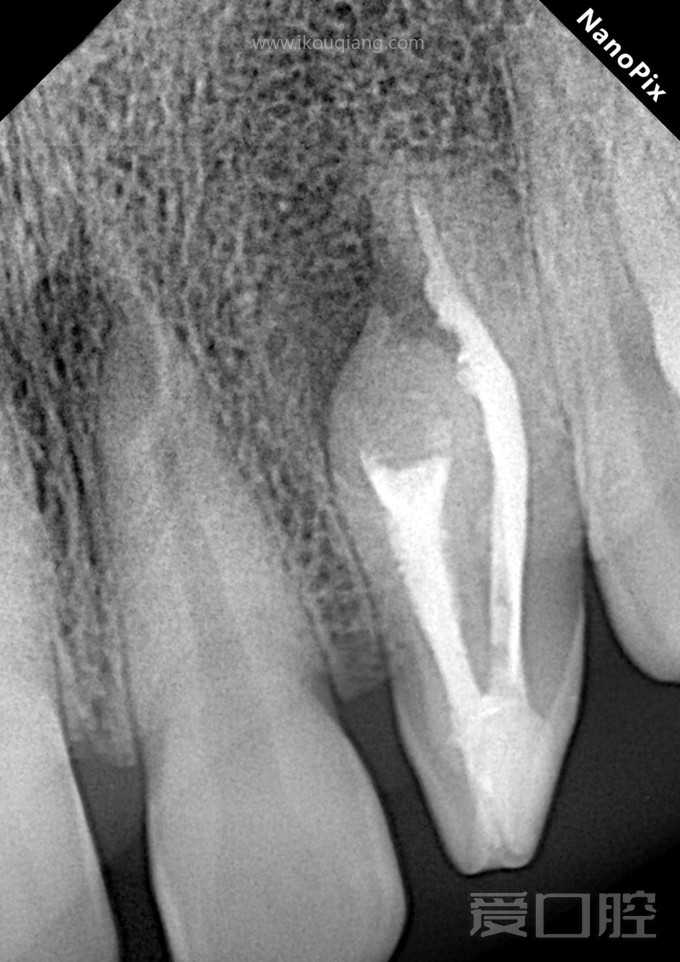

上2牙内陷根充1例

by Zainab Hussien Alzaidy